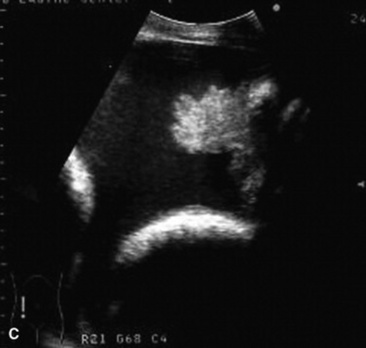

C. immitis is a soil saprophyte that grows in semiarid areas with sandy, alkaline soils.375 Inhaled arthroconidia enlarge to form nonbudding spherules, which incite an inflammatory reaction in the lungs and lymph nodes.375 Horses have weight loss, fever, abdominal pain, and signs of respiratory disease (Fig. 31-26). Localized, recurring nasal granulomas also have been reported.376 Diffuse infections with granulomas in the lungs, liver, kidney, or spleen carry a grave prognosis.375 Przewalskii horses may be more susceptible.377

image image image

Fig. 31-26 A, Coccidiomycosis in a quarter horse mare with severe weight loss after a 3-month period in Arizona and Colorado. Ultrasound image of free (B) pleural fluid and (C) abdominal fluid.

Courtesy Jamie Murphy, Califon, NJ.

C. immitis is difficult to culture, and spherules may not be observed histologically from antemortem lung biopsies. However, serology is very useful to diagnose infection, and decreasing titers are associated with clinical improvement.332,375 Serum antibodies are detected rarely in healthy horses.378 Antifungal agents successful in treatment of infected horses include itraconazole and fluconazole.332,379